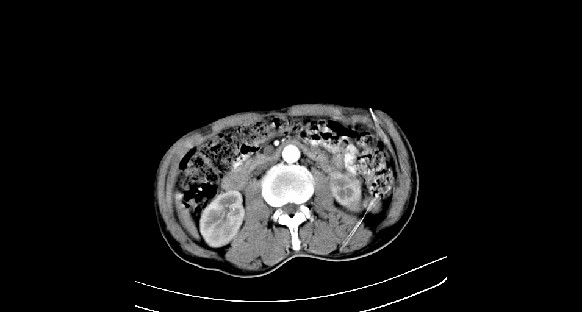

男性,70岁,体检b超发现左肾占位,请各位战友发表一下观点

左肾有两个病灶,且较大的病灶内可见点状钙化灶,增强扫描边缘也是呈渐进性强化,中央部分未见明显强化

考虑左肾脏错构瘤可能,不除外肾癌。